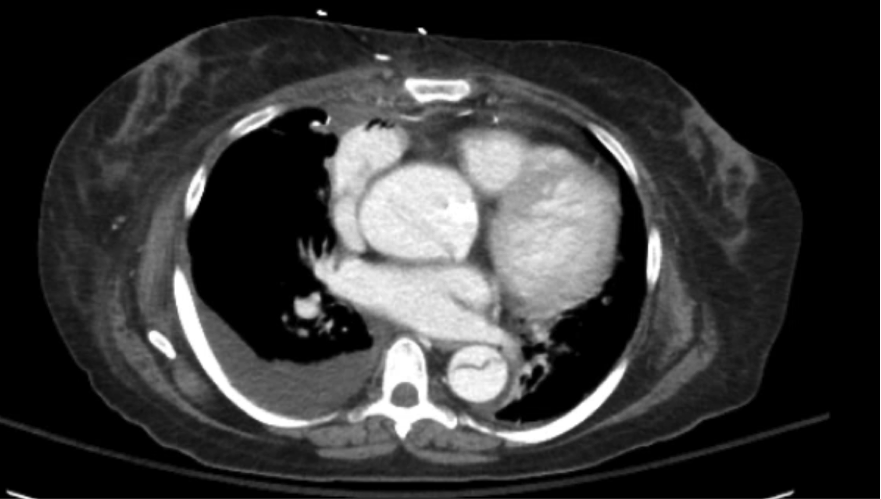

A 45 you female presents complaining of abdominal pain and back pain. She apears uncomfortable and she has hypertension on exam, otherwise vital signs are normal and exam is unremarkable. A CT is completed. What's the diagnosis? Scroll down for answer.

Answer: Aortic Dissection

- A flap is clearly seen in the descending aorta